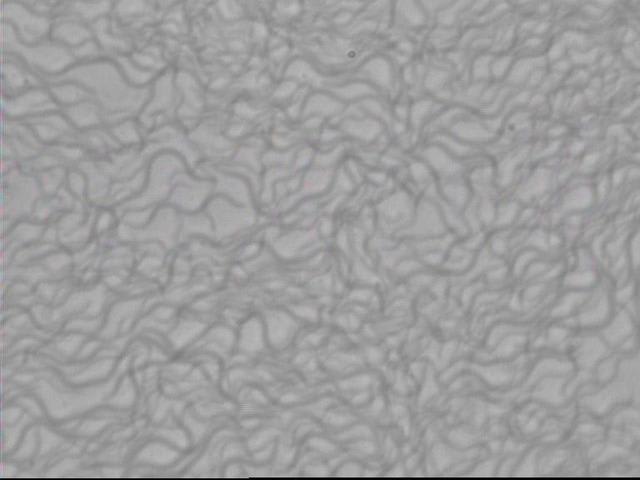

La microscopie initiale de ce cas.

Pas de très belles photos car les bestioles étaient trop vivaces et comme c'était le dernier rendez-vous, je ne me suis pas senti d'attendre trois ou quatre heures que leur activité baisse...

Beaucoup de spirochètes, des trichomonas, quelques entamoebas et des hématies liées au saignement spontané.